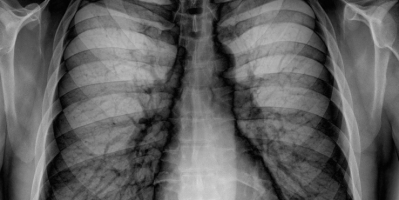

Radiology: Abnormal Chest X-Rays Part III

Radiology: Abnormal Chest X-Rays Part II

Radiology: Abnormal Chest X-Rays Part I

Radiology: Normal Chest X-Rays